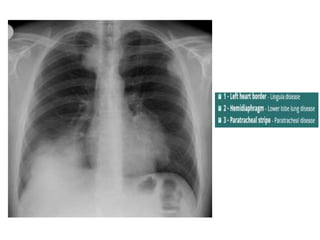

Silhouette Sign

• An intrathoracic lesion touching a border of

the heart, aorta, or diaphragm will obliterate

that border on the radiograph.

• An intrathoracic lesion not anatomically

continous with a border of one of these

structures will not obliterate that border.

• Eg. Lower lobe pneumonia, disease of lingula

Upper lobe consolidation

Middle and Lower lobe consolidation

Left lower lobe consolidation